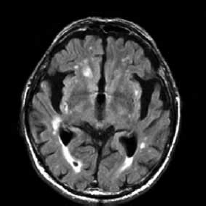

Paciente de 72 anos é referida ao consultório neurológico com queixas progressivas de perda de memória, alterações no comportamento e dificuldade em realizar tarefas diárias complexas, observadas pela família nos últimos dois anos. A avaliação cognitiva estruturada revela déficits significativos na memória episódica, funções executivas e orientação visuoespacial. O exame neurológico é notável por marcha apráxica e presença leve de rigidez axial. A ressonância magnética (RM) encontra-se a seguir.

Com base nesses achados clínicos e radiológicos, das seguintes condições, assinale a que representa, corretamente, o diagnóstico mais provável.